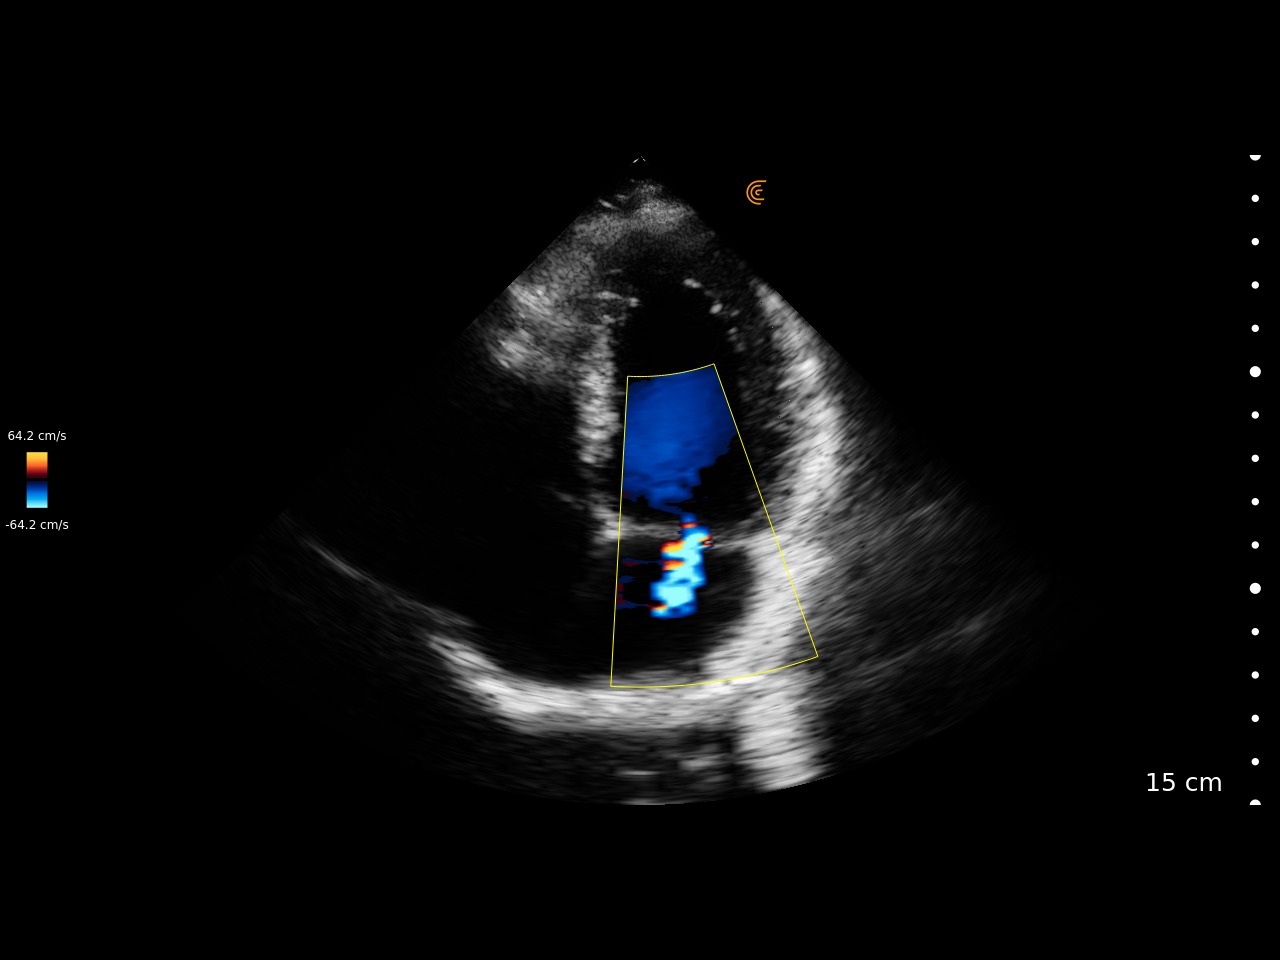

Medical professionals love the high portability, easy of use, and high-definition imaging of the Clarius C3 HD3 multipurpose scanner for full body imaging up to 40 cm. It’s the leading choice for medical professionals looking for premium imaging in an affordable scanner. Artificial intelligence, specialized presets and customizable workflows automatically optimize imaging for a seamless experience.

Applications: Abdominal, Cardiac, Lung, OB/GYN, Superficial

Clinical Images